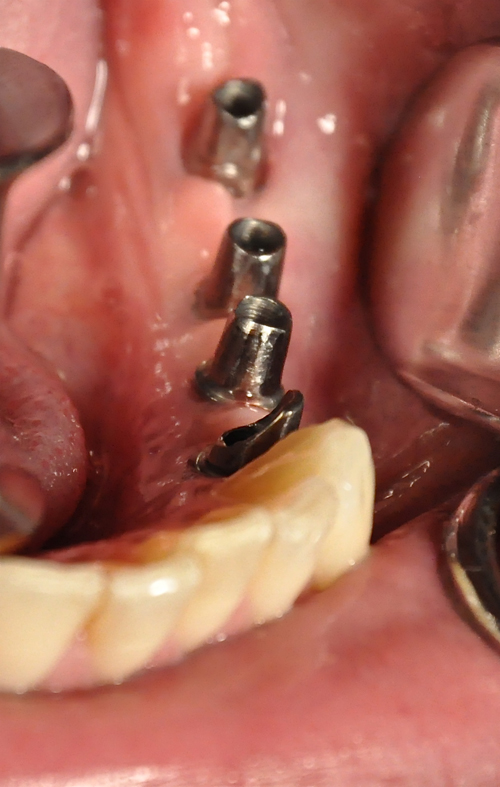

Palabras Clave: ELG: Estereolitográfico OH: Oclusión Habitual ORC: Oclusión en Relación Céntrica Paciente de 35 años de edad ,sexo masculino que lo derivan para implantar el tercer cuadrante. A la auscultación presenta ruidos articulares de tipo chasquido que remiten temporalmente luego de limitación de apertura bucal y maniobras quinesiológicas distractoras. También se observan recidivas de caries en algunos empastes y falta de disclusión canina de ambos lados. Se estudia el caso desde un punto de vista clínico, scanografico mediante Dentascan y tridimensional mediante montaje en articulador. A partir del scanner se obtienen datos para confeccionar modelo estereolitográfico (ELG),operar en el y construir férula quirúrgica dento-muco soportada. Habitualmente se procede directamente a implantar, dado que ese era el requerimiento del profesional derivante y el deseo del enfermo. Sin embargo, esa actitud enmascararía otro tipo de problemas que la boca presenta. Se consulta al odontólogo derivante, y coincide con mi opinión acerca de que si solo se lo implanta, sin corregir la posición mandibular, la situación de las ATMs, los empastes sin anatomía y la falta de disclusiones, el resultado final no será el deseado y su eficacia masticatoria no funcionará optimamente. Consultado el paciente coincide y acepta ese concepto y entonces procedemos a confeccionar un Jig de Lucia a partir del montaje de estudio, y lo dejamos puesto en boca toda la noche anterior a la consulta, para proceder a realizar un ajuste oclusal al día siguiente sin engramas anteriores, lo que facilita no tener que relajar nuevamente con laminillas de Long. En esta etapa pierde el implante correspondiente a la pieza 4.7 que traía en boca. Estabilizado el sistema, procedemos a la parte quirúrgica, comenzando por instalar la férula, retirar opérculos gingivales mediante bisturí circular, fresado óseo e instalación de implantes ,toma de impresión a cubeta fenestrada (pegando con metacrilato sin cambios dimensionales, los transfers a la cubeta especialmente diseñada.(1º método de pasividad protética utilizado), e instalación de tornillos de cicatrización. Inmediatamente de retirada la cubeta de boca y colocadas las réplicas de los implantes, procedemos a ferulizar los “ápices” de las réplicas para que no sufran movimientos durante el llenado de la impresión.(2º método de pasividad protética utilizado). Controlamos radiograficamente Tres meses después, procedemos a tomar nuevos registros de arco facial, registros intermaxilares en Oclusión en Relación céntrica, montaje de los modelos obtenidos intra operatoriamente y confección de un conjunto de cuatro coronas provisionales de metacrilato en el sector implantado y las correspondientes al maxilar superior. Verificada la perfecta función de todos los componentes, ausencia de todo tipo de síntoma y comprobada la paz en todo el sistema, procedemos tiempo después a confeccionar las fundas definitivas, que constituyen el “cerrojo” de la dinámica del mismo. Por último, corroboramos la oclusión fundamentalmente en lo que hace a la: